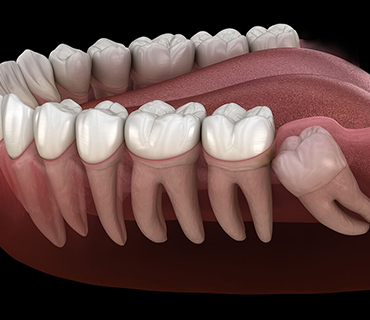

Wisdom Tooth Removal

- Wisdom teeth are the third molars that are last to erupt in your mouth

- Sometimes the wisdom teeth remains intact in the soft tissues & particularly seen above the gums. This may lead to entering of bacteria causing infection, pain & swelling.